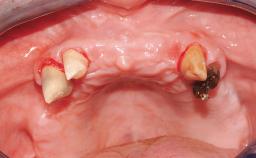

A 63-year-old female patient was referred to the University Medical Center in Groningen, Netherlands, for dental implant treatment. The patient had been edentulous in the upper jaw for 20 years. The remaining teeth in the lower jar had been removed two years before the consultation. The patient was wearing her first maxillary denture and her second mandibular denture; the latter was 1 year old at the time. The conventional upper denture had functioned satisfactorily for many years, but the patient complained about reduced stability and insufficient retention of her lower conventional denture. Her medical history revealed no significant findings. The intraoral examination revealed minor resorption of the maxillary alveolar process and extreme resorption of the mandibular alveolar process.

Defining Characteristics Fully edentulous lower jaw to be rehabilitated with two or more implants

Bone Volume Horizontally and vertically sufficient